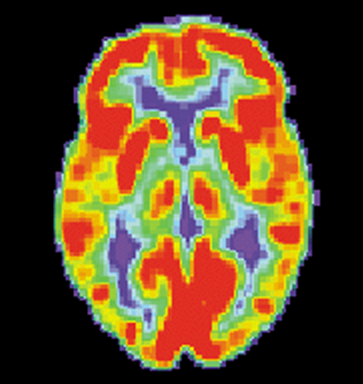

PET是一种核成像技术,用于医学中以观察不同过程,例如血液流动,新陈代谢,神经递质。

"这张照片展示了一个典型的PET设备,配备了ECAT Exact HR + PET扫描仪,像这样的PET扫描仪正逐渐被将PET和CT扫描仪组合为单个PET / CT成像设备的系统所取代。"[9]

少量放射性物质(称为放射性示踪剂)被注入血流中,到达大脑。在大脑中,放射性示踪剂附着在葡萄糖上并产生一种称为氟脱氧葡萄糖(FDG)的放射性核素[10]。大脑使用葡萄糖,它会根据不同区域的活动水平而显示出不同的水平。PET扫描的图像是彩色的,其中活动较多的区域以较暖的颜色显示为黄色和红色。大脑的PET扫描通常用于检测癌症或其他疾病。

正常人脑的PET扫描